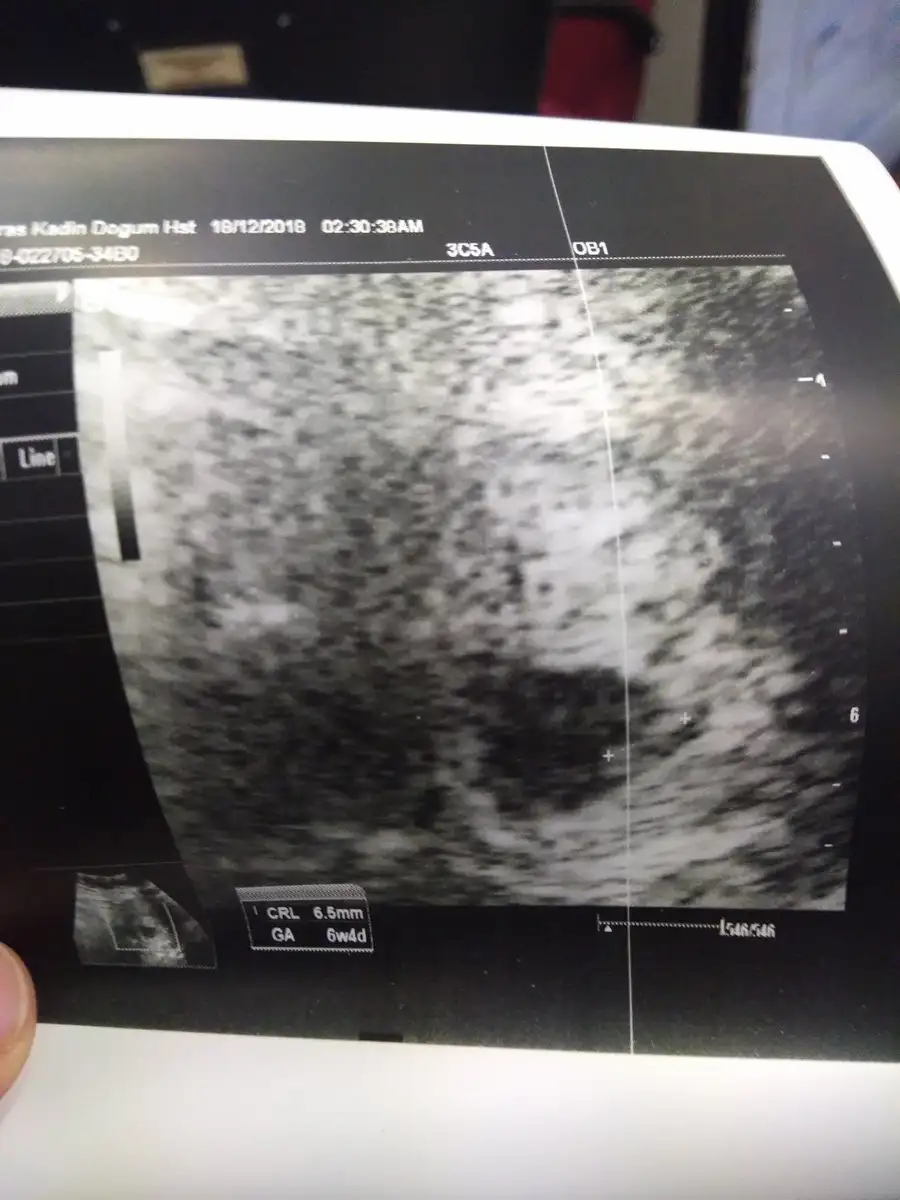

Erkek gibiSizce bebegimin cinsiyeti nedir?Eki Görüntüle 2214800 Eki Görüntüle 2214800